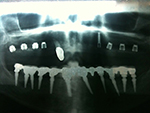

Die folgenden Patientenfälle sollen Ihnen einen Einblick in die Möglichkeiten der modernen Implantation geben.

Komplett-Implantation: